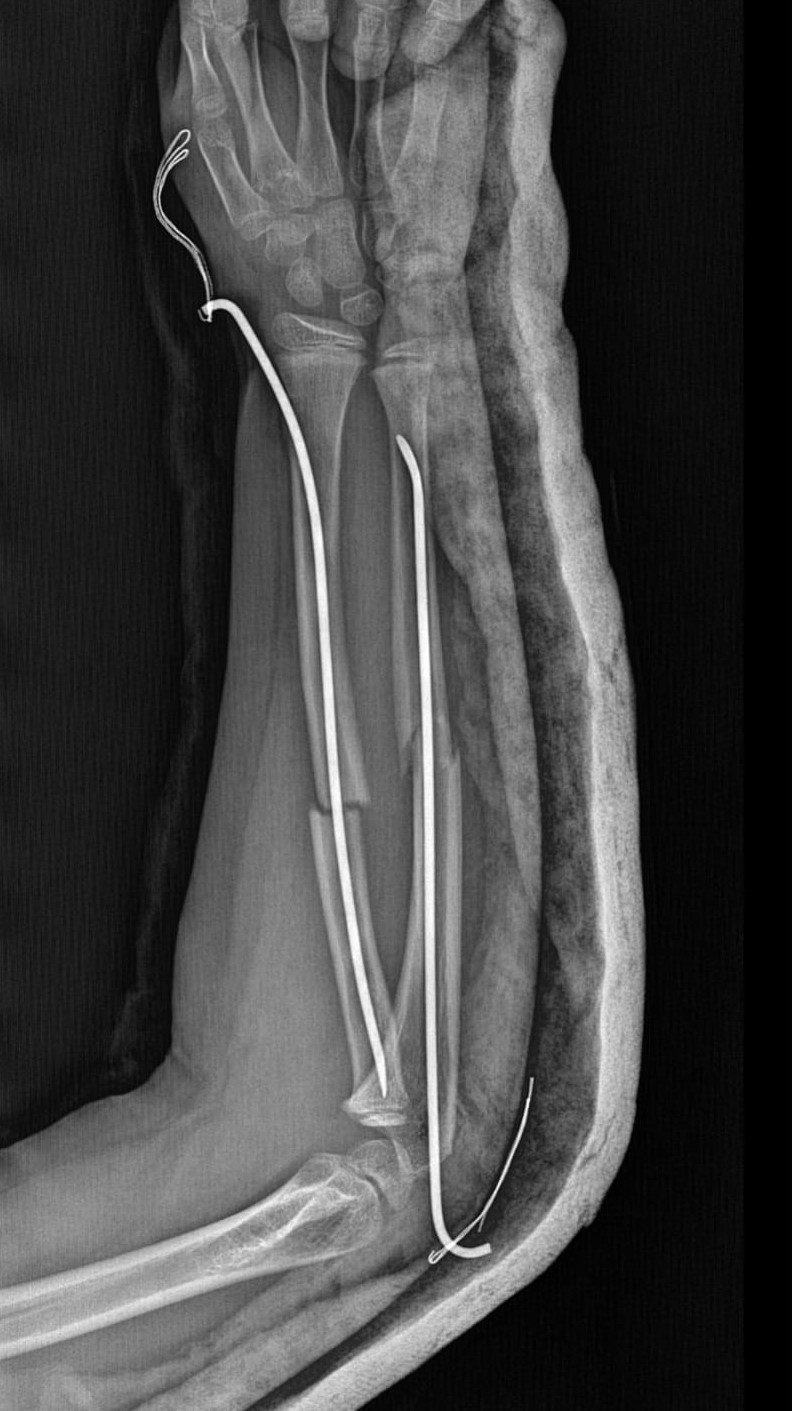

Olay, geçtiğimiz ay Büyükçekmece Tepecik'te bulunan bir ilkokulda meydana geldi. İddiaya göre Karamanlı 8 yaşındaki Y.K.Ş. okulda bir süredir kendisini rahatsız eden 9 yaşındaki çocuk tarafından darp edilerek kolu ikiye katlandı. Y.K.Ş.'nin 2'ye katlanan kolu 2 ayrı yerinden kırıldı. Öğretmenler Y.K.Ş.'nin ailesini arayarak, ‘oğlunuz arkadaşıyla kavga etti duvara çarptı' denildi. Oğlunu okuldan alıp hastaneye götüren anne Songül Gökdemir, oğlunun kolunun 2 ayrı yerinden kırıldığını öğrenip ameliyata alınacağını duyduğunda büyük şok yaşadı. Konuyla ilgili anne Gökdemir savcılığa giderek şikayetçi oldu. Savcılıktan ise 'söz konusu Suça Sürüklenen Çocuğun yaşının 12'den küçük olduğu gerekçesi ile kovuşturmaya yer yoktur' kararı çıktı. Anne Gökdemir karara itiraz ederken mağdur Y.K.Ş. ise haftalardır okula gidemiyor. Eğitimi aksayan çocuğun 2 hafta sonra ise platinlerinin çıkarılması için yeniden ameliyata gireceği öğrenildi.

Yaşanan olayı anlatan Songül Gökdemir, " Arkadaşlarından darbe aldığını biliyordum. Ayrıca Eylül ayından bu yana bir arkadaşının onun kolunu kırmaya çalıştığını söyledi. Ben de 'arkadaşını öğretmene söyle' dedim. Bundan kaçıyordu. O gün de rehber öğretmenine bu arkadaşını şikayet ettiler. Ben işe gittim 1 saat sonra öğretmeni aradı. Oğlunuz arkadaşıyla birbirini itekledi kolunu duvara çarptı gelir misiniz ?' dedi. Kendi imkanımla hastaneye götürdüm. Okula gittiğimde de oğlum derste oturuyordu. Öğretmen ders işliyordu ambulans çağırılmamış. Hastanede kolunda 2 tane kırık olduğunu acilen de ameliyata girmesi gerektiğini öğrendim. 3 gün sonra ameliyata alındı. Kolundaki platinlerden dolayı her gün pansumanı var. 2 hafta sonra tekrar ameliyatı var" dedi.